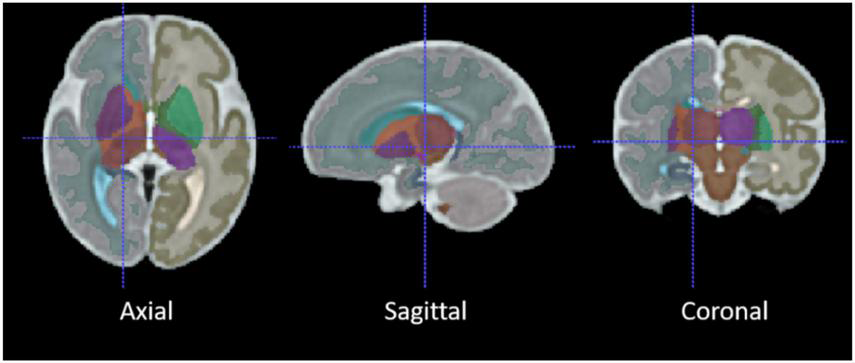

Two different registration toolkits were applied to the reconstructed images and compared to determine an optimal fetal subcortical segmentation strategy. Deformable registration was performed using ANTs (Avants et al., 2008) using the well-known SyN (symmetric image normalization) method, and linear (affine) atlas registration was performed using FLIRT (Jenkinson et al., 2012). The fetal brain atlas (Figure 3; Gholipour et al., 2017) is an averaged atlas from fetuses imaged at 36 weeks GA with predefined labels of deep-brain structures, including the thalamus and cerebellum. The atlas was nonlinearly and linearly registered into the native participant 3D MRI space. The transformation matrix was saved and applied onto the atlas mask to warp the tissue labels into subject space. The transformed atlas labels were used as thalamus and cerebellum masks and were compared with manual masks by calculating DSCs for the reliability test.

FIGURE 3

The average 36-week GA fetal brain atlas, including cerebellum and thalamus labels. The axial, sagittal, coronal, and 3D rendered views of the age-appropriate fetal brain atlas whereby deep brain tissues are color-coded.